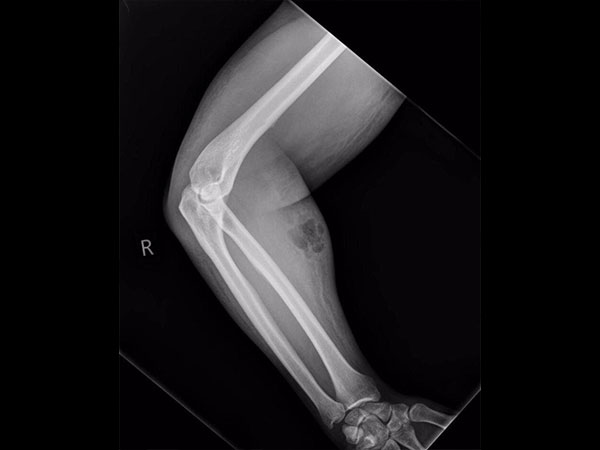

ബീജം കയ്യില് കുത്തി വച്ച പുള്ളിക്കാരന്

33 കാരനായ ഐറിഷ് യുവാവാണ് കഥാനായകന്. ഡബ്ലിനിലെ ആശുപത്രിയില് ഇദ്ദേഹം എത്തിയത് സഹിയ്ക്കാനാകാത്ത നടുവേദന കാരണമാണ്. എന്നാല് ഇയാളുടെ കൈത്തണ്ടയില് ഒരു ചുവന്ന പാടും തടിപ്പുമുള്ളത് ഡോക്ടര്മാര് ശ്രദ്ധിച്ചു.

ഇതേത്തുടര്ന്ന് എക്സ്റേ എടുത്തപ്പോഴാണ് കാര്യങ്ങള് വ്യക്തമായത്. നടുവേദനയ്ക്കു പരിഹാരമായി ഇദ്ദേഹം സ്വയം ചികിത്സ നടത്തി വരികയായിരുന്നു. എന്താണെന്നല്ലേ, സ്വന്തം ബീജം കൈത്തണ്ടയില് കുത്തി വയ്ക്കുക. ഒന്നും രണ്ടുമല്ല, കഴിഞ്ഞ 18 മാസങ്ങളായി ഇതേ രീതിയാണ് ഇദ്ദേഹം അവലംബിച്ചു വന്നിരുന്നതും. ഈ വ്യത്യസ്ത ചികിത്സാരീതിയ്ക്ക് അദ്ദേഹത്തെ പ്രേരിപ്പിച്ചതെന്തെന്നും വ്യക്തമല്ല.

അണുബാധ

ഇൗ ബീജങ്ങള് ഇദ്ദേഹത്തിന്റെ സോഫ്ററ് കോശങ്ങളില് കയറി അണുബാധയുണ്ടാക്കിയിരുന്നു. ഇതു കാരണം സെല്ലുലൈറ്റ് എന്ന അവസ്ഥയും ഇദ്ദേഹത്തിനു വന്നു. ചര്മത്തില് അണുബാധയും ഇതു കാരണമുണ്ടായി.